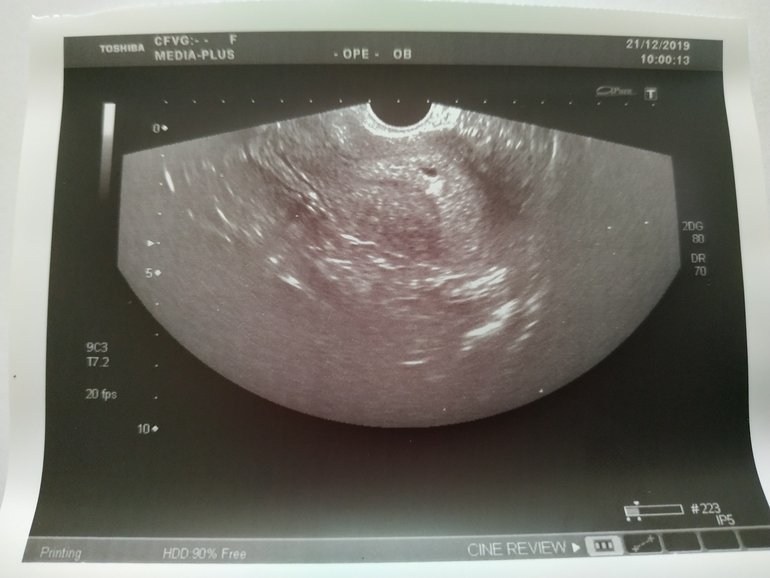

УЗИ, сказали не соответствует строку (

У меня тоже сейчас не соответствует, думала идет 8я неделя, я шла ток 7я.просто поздно зачатие произошло

У Вас хоть на неделю, а тут на целых 2.5-3, я в шоке ( Будем надеяться, что все будет хорошо!

Я не пойму вообще как она считает, если по акушерским, то 2,5 недели это вообще ничего, ещё наверное и оплодотворения нет, даже в 28 дневной цикл. А если по эмбриональному, тогда ляля соответствует сроку, но мне четко сказали, должно быть 5 недель, а плодное яйцо не соответствует.

У меня немного похожая ситуация. Был всего 1 па, поэтому вариантов не много, я ей это обьяснила, она говорит, типа где-то плавали видимо... Как я поняла, до 4 недель после оплодотворения еще нет желточного мешочка - это такой маркер для них. Если у вас 3 недели после оплодотворения, то типа 5 недель, а если от овуляции до оплодотворения была пара дней, то нет этих 5 недель акушерских.

Я ходила на 24 дпо, увидела пя в матке, написала 3-4 недели. Сказала прийти через 2 недели. Я тоже говорю, что такой маленький, она - нет, меня все устраивает.